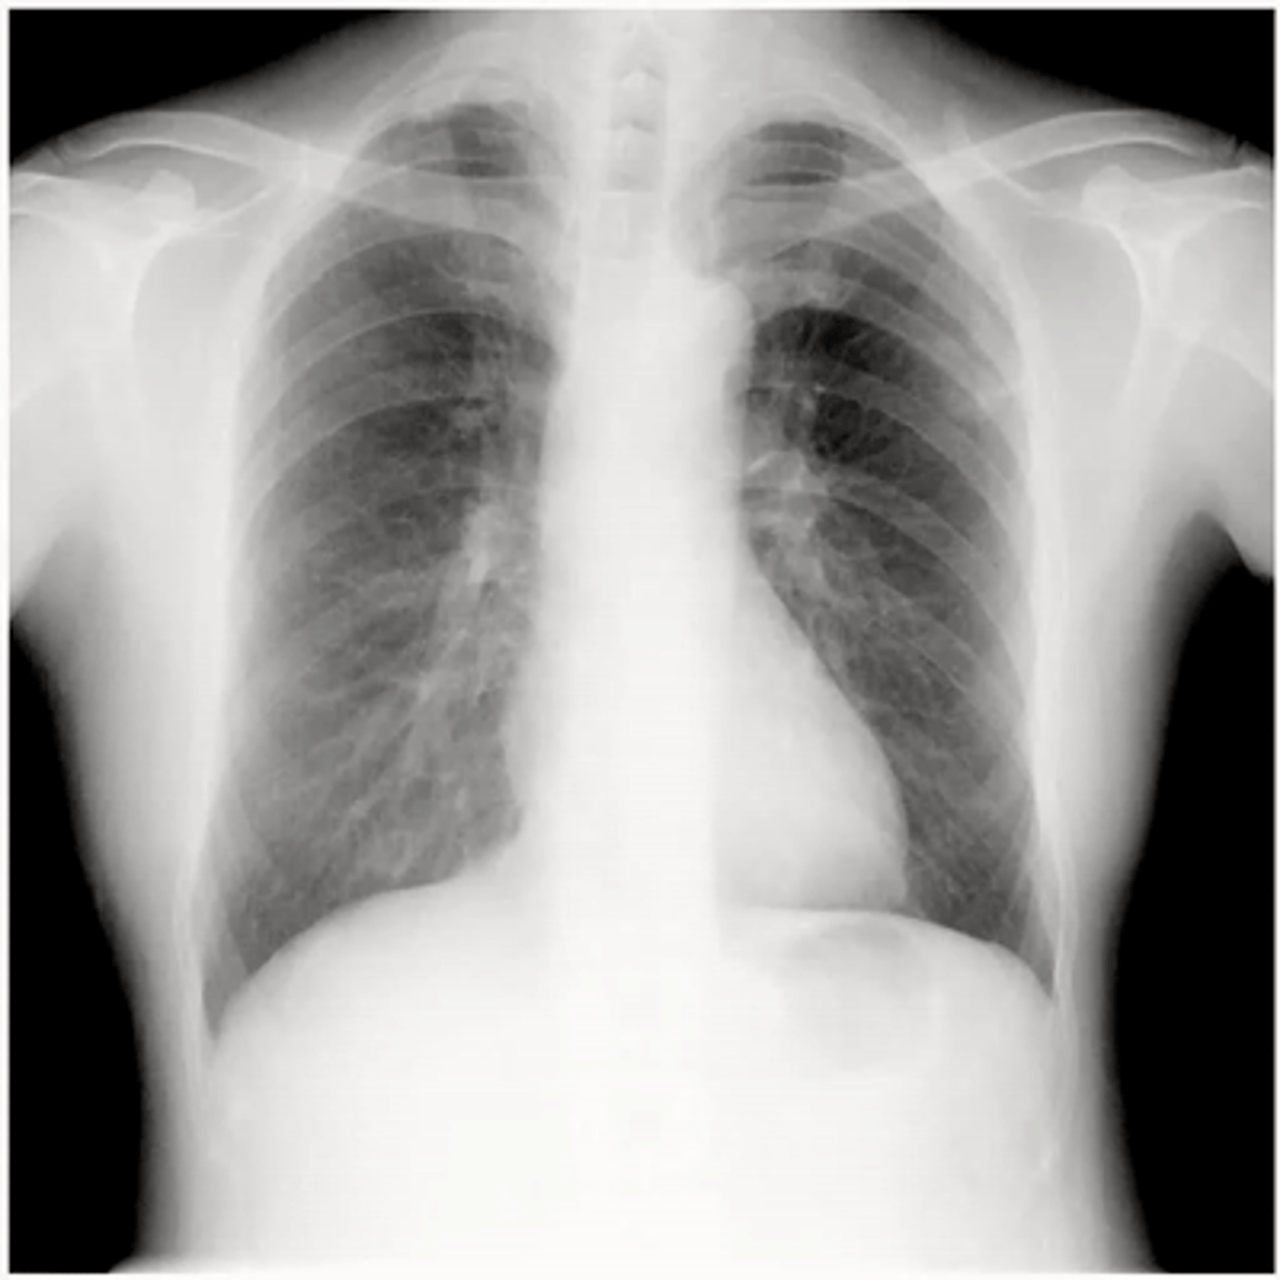

Visualisierung von quantitativen Daten der Zwerchfellbewegung und dem Lungenfeldbereich

DDR liefert quantitative Informationen über das Lungenvolumen und die Zwerchfellmobilität, die für die Therapiebewertung verschiedener Atemwegserkrankungen wie COPD, Asthma usw. verwendet werden können.

DDR zeigt auch im kardiovaskulären Bereich seine Leistungsfähigkeit. Ohne Einsatz von intravenösem Kontrastmittel oder Radiopharmaka liefert DDR funktionelle Informationen über die Lunge auf der Grundlage von Signalveränderungen im Zusammenhang mit dem Lungenkreislauf und der Belüftung. Somit kann DDR ein diagnostisches Instrument zur Identifizierung von Durchblutungsstörungen sein, die mit pulmonalen Thromboembolien in Zusammenhang stehen.

Dynamic Digital Radiography (DDR) ist eine neue Technologie im Bereich der konventionellen Radiographie, mit der sich komplexe anatomische Bewegungen mit niedriger Strahlendosis visualisieren lassen. Mittels gepulster Strahlung wird eine Serie von Aufnahmen (Cine loop) erstellt und in der neu konzipierten DI-X1 Workstation durch verschiedene Algorithmen ausgewertet. So können in einem einzelnen Arbeitsgang gleich mehrere Fragestellungen beantwortet werden, ohne dass zusätzliche Untersuchungen nötig sind.

Mit DDR lassen sich in Kombination mit dem mobilen Röntgensystem AeroDR TX und den leistungsstarken AeroDR 3 G5-Detektoren bis zu 15 aufeinanderfolgende Röntgenbilder pro Sekunde aufnehmen, die anschließend zur weiteren Bearbeitung an die speziell für DDR entwickelte Bildgebungs-Workstation DI-X1 übertragen werden. Es können sowohl physiologische Zyklen als auch einzelne Röntgenbilder bis zu einer Größe von 43 × 43 cm erzeugt und betrachtet werden. Damit liefert DDR erheblich mehr Informationen als herkömmliche statische Bilder und bietet für die mobile Radiographie auf Intensivstationen und in Operationssälen den großen Vorteil, dass die zu untersuchende Person im Bett verbleiben und auf die Einnahme von Kotrastmitteln oder Radiopharmaka verzichtet werden kann. Mit einer Untersuchung, die bis zu 20 Sekunden dauert, erhalten Ärzte unterschiedliche Auswertungen, die ihnen einen genauen Einblick in etwaige Pathologien ermöglichen. (Drahtlose Übertragung von seriellen Aufnahmen)